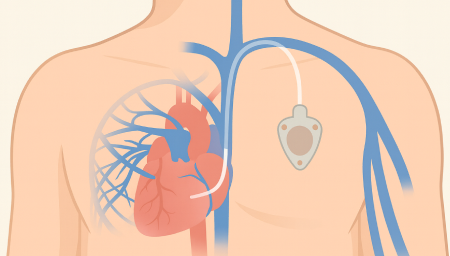

Chemoport는 항암제처럼 자극이 강한 약물을 안전하고 안정적으로 투여하기 위해

흉부 피부 아래에 이식하는 중심정맥 사용 포트입니다.

Chemoport는 항암제처럼 자극이 강한 약물을 안전하고 안정적으로 투여하기 위해 흉부 피부 아래에 이식하는 중심정맥 사용 포트입니다. 팔 혈관이 약하거나 반복 주사로 인한 통증이 걱정되는 환자에게 도움을 줄 수 있으며, 장기간 치료가 필요한 경우 편안하게 항암 치료를 지속할 수 있도록 설계되어 있습니다.

항암관(Chemoport)삽입 과정

국소마취 후 작은 절개를 시행 (보통 쇄골 아래 약 2~3cm 정도 절개)

정맥에 카테터 삽입 후 포트와 연결

방사선으로 카테터 위치 확인

피부 봉합 후 소독 드레싱

Chemoport는 피부 아래에 완전히 이식되는 구조라 반복적인 바늘 찌름을 줄일 수 있고, 장기간 안정적인 항암제 투여가 가능합니다.또한 샤워 시에도 물이 닿지 않아도 되고, 외관 노출이 적어 일상생활에서 불편감이 비교적 적습니다.